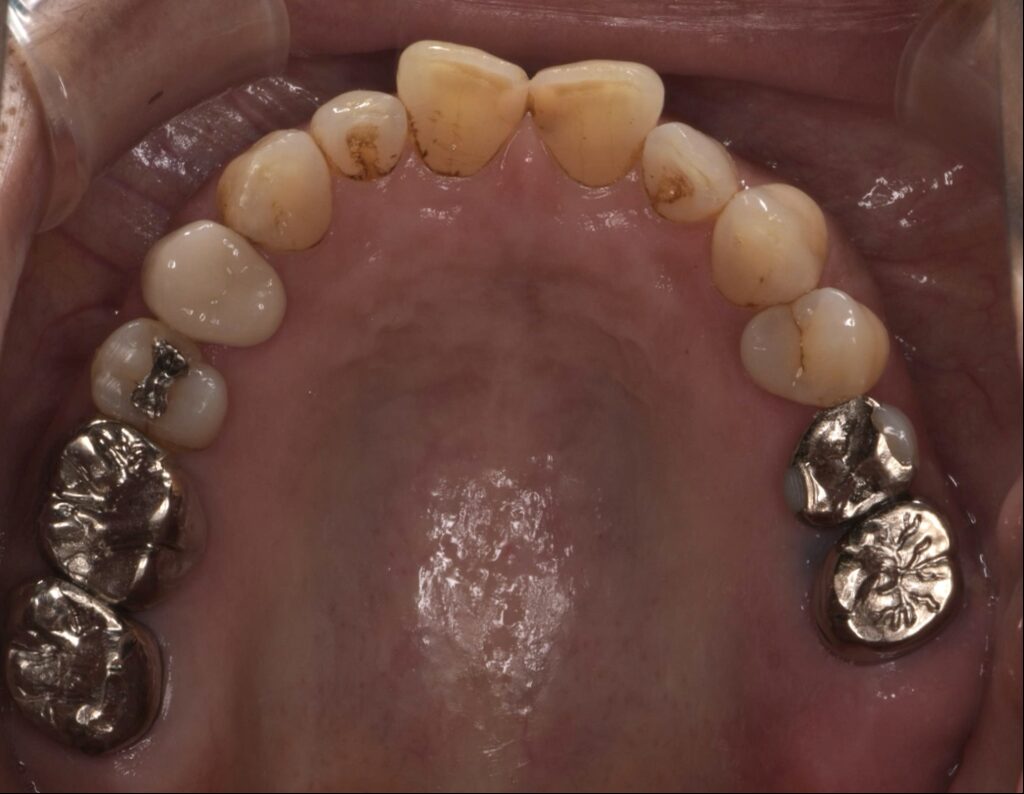

入れ歯が合わなくインプラント治療した症例

Before